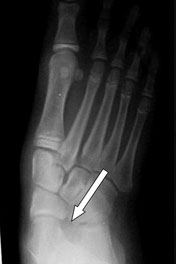

Physicians may evaluate the transverse plane component by noting the medial bulge produced by the uncovered talar head and the percentage of talar head coverage on an AP weightbearing radiograph.

Transverse plane deformity. These children stand with the calcaneus in 10 degrees of heel eversion. Subtalar range of motion averages 30 degrees of inversion and 10 degrees of eversion. When one views this from above, there is a major prominence of the talar head medially. This is confirmed on AP weightbearing radiographs. The medial half of the talar head is not covered because the navicular is placed dorsally and laterally. Supinating the rearfoot will cover the talar head but this results in an unacceptable varus position of the calcaneus.

Examination of her walking pattern reveals a normal heel-toe gait on both sides. The right foot is externally rotated about 15 degrees to the line of progression and the left foot is externally rotated about 10 degrees. Radiographs show a wide AP talocalcaneal angle with about 50 percent of the talar head uncovered and a global midtarsal fault.

Radiographs show a very wide AP talocalcaneal angle with an abducted forefoot. The lateral view shows sagittal instability of the medial column. The deformity is most pronounced on the transverse plane.

The AP and lateral weightbearing radiographs show marked widening of the AP talocalcaneal angle and severe midfoot collapse on a lateral radiograph.